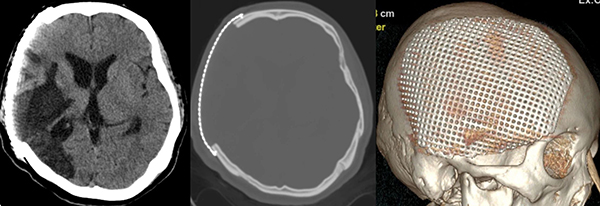

神经外科在接诊后,为患者完善头颅三维CT检查及钛网塑形,并为患者成功实施了颅骨修补成形术。术后10天拆除患者伤口缝线,头颅外形恢复了正常,无新发神经功能障碍,左侧肢体肌力进一步好转,为继续康复治疗创造了有利条件,目前已转院继续接受康复治疗。

▲经过预塑形的钛网

▲术后头颅CT显示钛网贴合满意